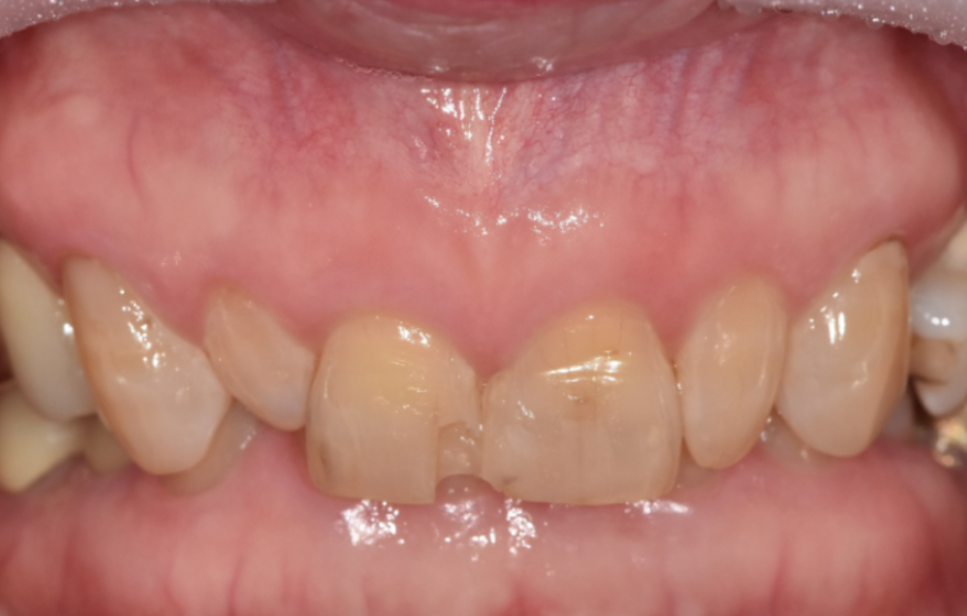

이 환자분은 70대 여성입니다.

젊을 때부터 앞니 사이가 벌어져 있었고

그 틈을 레진으로 메워 사용해 오셨다고 해요.

처음에는 괜찮았지만 나이가 들며

레진이 깨지고 떨어지는 일이 반복되자

“이번에는 제대로 고쳐보고 싶다”며 내원하셨습니다.

입안을 자세히 보니

앞니 사이를 메운 레진이 깨져 있었고,

그 양옆 작은 앞니가

다른 치아보다 눈에 띄게 작았습니다.

이렇게 주변 치아보다 유난히 작은 치아를

‘왜소치’라고 부릅니다.

왜소치는 크기가 작다 보니

그 주변으로 공간이 남기 쉽고,

결국 앞니 사이가 더 벌어져 보이는 원인이 됩니다.